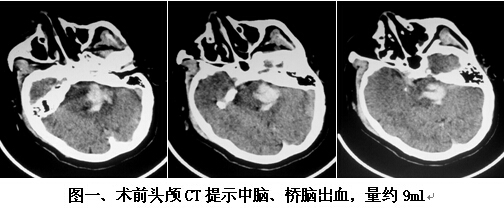

患者男,63歲,因突發(fā)神志不清2小時(shí)入院。入院時(shí)神志呈淺昏迷狀,頭顱CT提示腦干出血(橋腦、中腦區(qū)域,量約9ml)(見圖一)。神經(jīng)外科鐘三寶主任醫(yī)師查看患者后,分析患者病史、臨床表現(xiàn)及體查,結(jié)合影像學(xué)結(jié)果,考慮患者為重癥高血壓性腦干出血,需開顱行腦干血腫清除術(shù)。在發(fā)病后6小時(shí)左右,由鐘三寶主任醫(yī)師主刀,帶領(lǐng)李遠(yuǎn)志副主任醫(yī)師為患者進(jìn)行了手術(shù)。根據(jù)Brown兩點(diǎn)定位法則,采取枕下乙狀竇后入路,手術(shù)頭皮切口設(shè)計(jì)為勾型,骨窗大小約3cm*4cm(見圖二),術(shù)中清除腦干血腫約10ml,手術(shù)非常成功。術(shù)后復(fù)查頭顱CT提示腦干血腫基本清除(見圖三)。